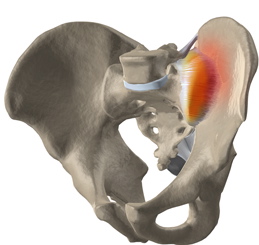

Sacroileita este denumirea imagistic? pentru inflama?ia articula?iei sacroiliace.

Să revenim acum la sacroiliită. Ea se poate exprima clinic sub formă de durere de spate joasă sau durere în fese, cu iradiere pe membrul inferior. Durerea este de obicei agravată de statul în picioare prelungit sau urcatul scărilor. Sacroiliita este o manifestare a spondilartropatiilor (spondilită anchilozantă, artrită psoriazică, artrită reactivă) și a artritei asociată bolilor inflamatorii intestinale (boală Crohn, colită ulcerativă). Alte cauze ar fi traumatismele, osteoartrita (degenerativă), infecțiile sau sarcina. Diagnosticul se pune pe baza imagisticii osteoarticulare – radiografie, CT sau IRM. Tratamentul este al bolii de bază și simptomatic (repaus, terapie fizicală și antiinflamatoare).